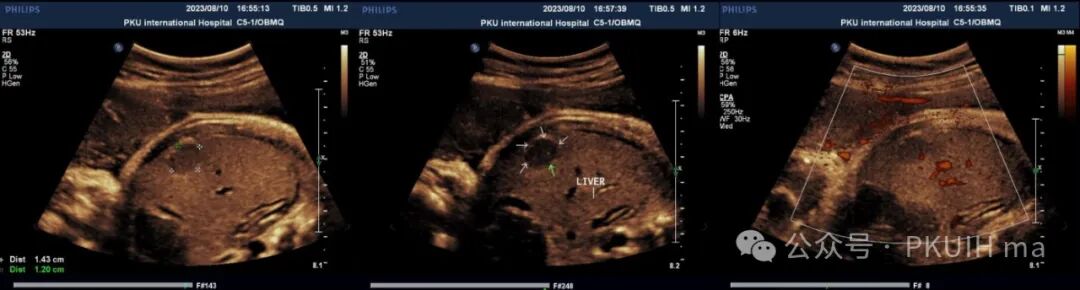

上图是一例孕晚期发现肝内实性占位,在出生后的随访中一直无明显变化,初步考虑是肝血管瘤。